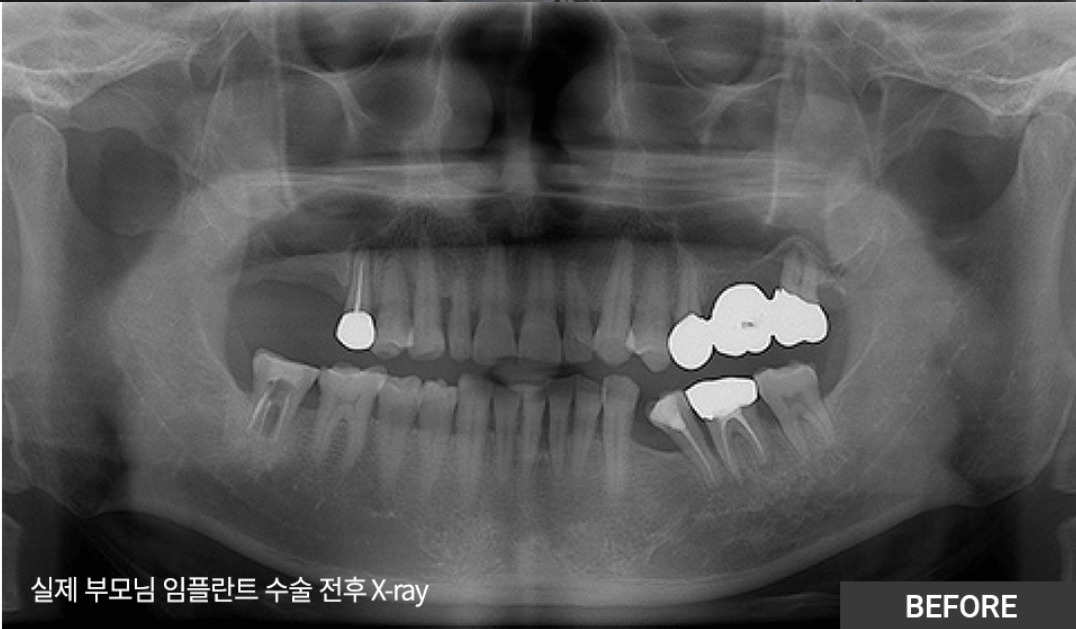

| 아버지께서 동네치과에서 임플란트 2개 진단 받았는데 신뢰가 안가서 다른 치과 알아보던 중에 친구가 추천해줘서 석플란트 치과 진료 받아보니 1개만 예약 완료했네요. 1개만 하셔도 문제 없고 불편함 없다고... 👉더보기 |